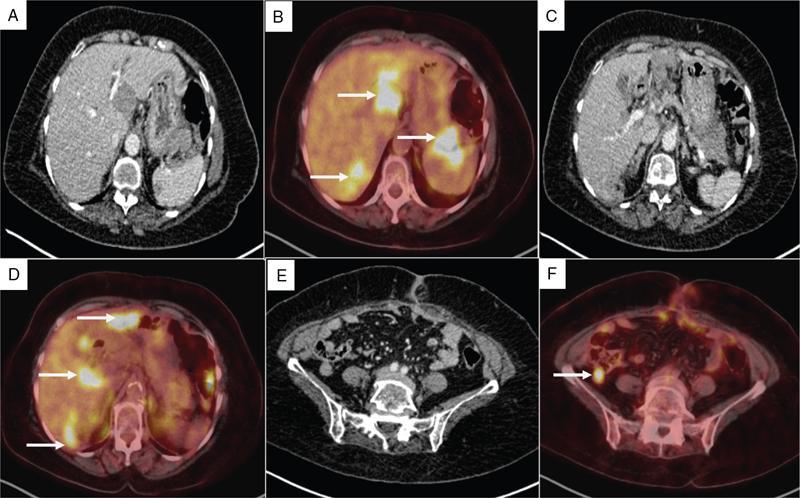

Shivsamb Jalkote, Slesha Bhalja, Disha Lokhandwala, Mansi Jantre, Karthik Ganesan Peritoneum is involved in a diverse group of primary as well as secondary pathologies ranging from the infective/inflammatory spectrum to malignancies. Peritoneal diseases are both common and potentially life threatening, and yet often get neglected in routine evaluation, due to the complex peritoneal anatomy and sometimes subtle imaging manifestations. The radiologist forms an integral part of the multidisciplinary team dealing with peritoneal pathologies and hence, having a lucid understanding of peritoneal anatomy, pathways of disease spread and different treatment options is paramount for an accurate radiological analysis. All three major serosal cavities (pleural, pericardial and peritoneal) of the body are derived from a single coelomic cavity, which is lined by a continuous mesothelium. At 2 weeks of gestational age, during the gastrulation stage, the embryo is a trilaminar disc, composed of the endoderm, mesoderm and ectoderm. During this stage, the development of the coelomic cavity commences as a consequence of morphological changes in the mesodermal cells leading to a coalition of the intercellular spaces. Peritoneum originates from mesoderm with its parietal layer developing from somatic mesoderm and visceral layer developing from splanchnic mesoderm. Initially, the peritoneum is an empty sac into which the growing gut tube protrudes (at 3 weeks of gestational age), resulting in the formation of the dorsal mesentery (formed by the fusion of two layers of the splanchnopleuric mesoderm) by which the gut tube is suspended lengthwise. The mesodermal cells opposed to the gut tube represent the future visceral peritoneum and those lining the body wall and the septum transversum form the future parietal peritoneum. Analogously, the ventral mesentery originates from the mesoderm of the septum transversum with the closure of the anterior abdominal wall, and, is short and not as extensive as the dorsal mesentery. The two mesenteries are aligned in the sagittal plane, subdividing the primitive peritoneum into right and left cavities, which are continuous anteriorly below the inferior edge of the ventral mesentery. With the development of various abdominal organs as buds from the gut tube, the capacity of the abdominal cavity diminishes, pushing the midgut loop into the umbilical cord. This physiologic herniation of the midgut takes place at the 6th week of gestation. Simultaneously, as the peritoneum drapes over the developing organs, there is compartmentalization of the cavity and a pattern of folds develops that eventually form the peritoneal ligaments. The majority of these ligaments arise from the ventral or dorsal mesentery. As the hepatic bud develops within the ventral mesentery, derivatives of the ventral mesentery can be divided based on their relation to the liver. The gastrohepatic ligament (lesser omentum) develops dorsally and the falciform, coronary, and triangular ligaments develop ventral to the liver. Conversely, the dorsal mesentery spans between the gut tube and the posterior abdominal wall, and the spleen and pancreatic tail develop within it. In congruence, it forms the gastrophrenic, gastrosplenic and splenorenal ligaments and peritoneal folds of the small and large intestines. As stated earlier, the dorsal mesentery has a relatively larger caudad extension and since the spleen develops in its upper portion, the rapidly growing mesentery beyond the spleen forms the greater omentum. Finally, the differential growth of the greater curvature of the stomach and the right hepatic lobe results in rotation of the abdominal organs and their mesentery, and the cephalad portion of the peritoneal cavity is divided into a larger ventral cavity, called the greater sac, which caudally communicates with the common peritoneal cavity, and a smaller dorsal cavity called the lesser sac. The key aspects of peritoneal development are summarized in Flowchart 8.6.1 and Fig. 8.6.1. Laparoscopy remains the gold standard in the assessment of peritoneal disease, however, it is an invasive technique, and has certain diagnostic limitations including the inability to assess parenchymal diseases, extraperitoneal diseases, and also has limited utility in the presence of adhesions. Hence laparoscopy is not recommended as the first-line modality and has been replaced by cross-sectional imaging in routine clinical practice. The role of imaging is primarily to assess disease burden in terms of volume and extent and to identify surgically nontreatable disease, which reduces open and shut laparotomies. Peritoneal metastatic disease burden is assessed using peritoneal carcinomatosis index (PCI) both surgically as well as using cross-sectional imaging, details of which will be discussed subsequently. CT, MRI and PET/CT are all commonly used imaging modalities, however, there is no singular universally accepted reference imaging standard for the peritoneal disease. In a recent meta-analysis evaluating the diagnostic performance of imaging in the detection of peritoneal metastasis (PM), authors concluded that MRI (DWI) and PET/CT show comparable diagnostic performance in gastrointestinal and ovarian cancer malignancies however the widespread availability of MRI makes it the more likely imaging modality of choice in the future. The results of this study are summarized in Table 8.6.1. Conventional imaging including radiography and barium studies have a poor diagnostic yield in evaluating peritoneal pathologies. Abdominal radiographs are usually restricted for identifying pneumoperitoneum and bowel obstruction in the setting of acute abdominal pain. Diffuse increase in radio-opacity of the abdomen, poor definition of soft tissue shadows (psoas, liver and spleen), bulging flanks along with medial displacement of small bowel loops from the properitoneal fat stripe are indirect markers of large ascites which can prompt further evaluation with ultrasonography. Indirect features of peritoneal disease on barium studies include mass effect and displacement of adjoining bowel loop, narrowing of bowel loop with bowel dilatation along with nodularity, spiculation, or tethering of adjacent mucosal folds or haustra with sacculation of the uninvolved contralateral border. Barium studies have fallen out of favour in routine radiological practice owing to the widespread use of cross-sectional imaging. Ultrasonography (US) is a readily available and relatively inexpensive imaging tool. Traditionally its role in the evaluation of peritoneal pathologies is limited as US beam gets strongly reflected at the interface of air and visceral structures which leads to obscuration of underlying structures. US remains the primary imaging modality in the evaluation of an acute abdomen and is useful in detecting of ascites, focal lesions and any focal abnormality at the site of tenderness. US has the unparalleled advantage of providing real-time assistance in performing imaging-guided procedures such as paracentesis and peritoneal biopsies. US can be used in characterization of focal lesions (as solid, solid-cystic and cystic) and assessment of internal vascularity using colour Doppler. Transvaginal US provides a good overview of pathologies involving pouch of Douglas besides the uterus and adnexa. Experienced and skilled sonologists can detect omental thickening, peritoneal nodules and small surface deposits using high-frequency transducer (Fig. 8.6.2). Endoscopic US allows assessment of diseases involving peritoneal ligaments besides assistance in a guided biopsy. The reported sensitivity, specificity and accuracy of EUS-FNA versus CT/MRI in detecting PM was 91% versus 28%, 100% versus 85% and 94% versus 47%, respectively. CT is the most commonly employed imaging modality in the evaluation of peritoneal pathologies due to its widespread availability, fast acquisition and high spatial resolution. Current generation multidetector CT scanners (64 slices and above) offer very thin collimation, leading to the acquisition of near isotropic volumetric data which allow reformations in coronal and sagittal images without any added imaging time. It is the modality of choice for preoperative staging in most primary abdominal and pelvic malignancies (e.g. stomach, appendix, ovary) owing to its ability to detect local and regional infiltration, nodal involvement and distant metastases. CT is also used to evaluate PCI and detect disease in critical and occult locations, thus significantly altering further management strategies. CT is the most common imaging modality used in postoperative surveillance and evaluation of postoperative recurrence. CT protocol includes administration of both enteric contrasts (oral and rectal) and intravenous contrast (Table 8.6.2). Optimal bowel distension is key as collapsed loops can mimic disease and also mask the serosal and endoluminal disease. Often, a CT scan of the chest is performed as an adjunct to rule out pleuroperitoneal/transdiaphragmatic dissemination. Helical (≥64 slice scanner) Dual energy scanner if available As thin as possible (≤1 mm) Same as section thickness without gap From xiphisternum to pubic symphysis Chest included if suspicion of thoracic involvement 1 L of positive oral contrast over duration of 60 minutes and 500 mL of positive rectal contrast on table before administration of IV contrast 1.5–2 mL/kg of nonionic contrast with high iodine concentration (≥ 300) at rate of 3–5 mL/sec Unenhanced imaging not recommended. Monophasic acquisition at 60 seconds usually sufficient in majority cases Arterial phase at 20 seconds acquired for arterial assessment Delayed phase in cases of ureteric obstruction, slow bowel transit and suspected leak. Axial 1 mm thickness, multiplanar reformats in coronal and sagittal planes at 1 mm MIP or 3D volumetric sections for vascular assessment There is a wide range of reported diagnostic accuracy (sensitivity ranging from 25% to 100%, specificity ranging from 78% to 100%) of CT in the assessment of PM depending on the expertise of the reader and scanner type. In general, key factors affecting CT sensitivity include the size of lesion, the region of affection and presence of ascites. 64 slice scanners with multiplanar reformations allow 100% sensitivity and positive predictive value in detecting lesions measuring >5 cm, which partly diminishes for lesions between 0.5 cm and 5 cm in size with sensitivity and positive predictive being 83% and 93%, respectively. It receives the most criticism in the evaluation of lesions < 0.5 cm with significantly low sensitivity and positive predictive value (43% and 76%, respectively). There is also a great degree of variation in sensitivity based on the anatomical location of the disease. In a study by Koh et al., the detection rates ranged from 8% to 67%, depending on the region involved; only the epigastrium exceeded 60%, with the small-bowel disease being the most poorly visualized (8%–14%). The sensitivity for tumour detection in epigastrium, greater omentum and under surfaces of the diaphragms was 60%–90%, while it was 50%–70% in the retroperitoneum and pelvis, and small bowel-mesentery involvement was detected in merely 20%–50% of cases. These are noteworthy findings, as small-bowel involvement has major implications on outcome and is one of the limiting factors for complete cytoreduction. Poor soft tissue resolution of CT doesn’t allow accurate differentiation between mucinous deposits from ascites. Administration of positive enteric contrast can mask calcified serosal deposits. DECT uses two separate x-ray energy spectra and allows characterization of tissues based on their differences in attenuation properties at different energies. Though the role of DECT in the assessment of abdominal pathologies is increasingly reported in the literature, there are very limited data available on its application in assessment of peritoneal pathologies. The combination of iodine overlay with conventional imaging has shown a better specificity in differentiating PM from benign peritoneal entities, and hence can be particularly useful in the postoperative setting. MR imaging offers excellent soft tissue resolution, multiplanar capabilities and avoids exposure to ionizing radiation, making it an attractive tool for evaluation of peritoneal diseases. MRI is better suited and can be problem solving in visualization of smaller lesions (<1 cm) and assessment of relatively concealed areas such as subphrenic, mesenteric and bowel serosa. Unenhanced T1- and T2-weighted images can show larger peritoneal deposits and masses but are relatively insensitive for the depiction of smaller lesions. The combination of diffusion-weighted imaging (DWI) and delayed gadolinium-enhanced MR imaging is considered the most accurate technique for detecting peritoneal tumours (Fig. 8.6.3). MRI protocol for assessment of peritoneum has been detailed in Table 8.6.3. In a study by Low RN et al., MRI PCI correctly categorized tumour volume in 91% of patients compared to surgical PCI, as opposed to 50% with CT. In addition, MRI demonstrated per site sensitivity of 95%, specificity of 70% and accuracy of 88%, while CT showed a corresponding per site sensitivity of 55%, specificity of 86% and accuracy of 63%. MRI PCI has also shown to have better prediction of intraoperative burden of disease for invasive appendiceal and peritoneal mesothelioma histologies as compared to CT-PCI. *This general imaging protocol is based on 3 T MRI Siemens system, covers both abdomen and pelvis. Protocol is modified depending on primary disease and type of scanner. Low RN. Preoperative and surveillance MR imaging of patients undergoing cytoreductive surgery and heated intraperitoneal chemotherapy. Journal of gastrointestinal oncology. 2016 Feb;7(1):58. The higher cellularity of majority of peritoneal nodules results in restriction of water movement and corresponding high signal intensity on DW images. On the higher b-value images, bowel contents are suppressed and the serosal and peritoneal tumours become hyperintense. DWI is also useful to demonstrate associated lymphadenopathy, hepatic and osseous metastases. In a study by Zhang et al., in PC of colorectal carcinoma, DWI demonstrated sensitivity of 69.4%, 91.3% and 100% for lesions measuring <0.5 cm, 0.5–5.0 cm and >5 cm, respectively. The overall sensitivity, specificity and accuracy of DWI for the detection of peritoneal tumours were 80.3%, 84.5% and 82.1%, respectively. DWI/MRI is also superior in demonstrating lesions involving small bowel wall, with an accuracy of 92%–95% versus 48% for CT. Reported negative predictive value of DWI for small bowel serosal metastases is 100%. Whole-body DWI/MRI was highly accurate for the prediction of inoperability (PPV 100%, NPV 90.3%) and was capable of detecting metastases both inside and outside the abdominal cavity. Peritoneal tumours enhance slowly and are best depicted on the final set of images obtained about 5 minutes following gadolinium administration. The increased conspicuity of these enhancing peritoneal tumours improved detection of small tumours that are often missed on CT scans. For this reason, perfect breathhold is essential while obtaining the final set of images and if images are acquired later, contrast that has diffused into the ascitic fluid can obscure smaller lesions. The high-contrast conspicuity of fat-suppressed and delayed gadolinium-enhanced MRI makes it the imaging modality of choice in depicting subcentimetre deposits (including those measuring <5 mm), and also deposits in anatomically concealed sites (e.g., subphrenic, mesenteric and bowel serosa). Gadolinium-enhanced MRI has higher sensitivity in detecting peritoneal lesions <1 cm which is about 85%–90% compared to 22%–33% for CT. Despite the clear superiority of MRI over CT, the major detractors against MRI are the long exam times and the higher expense burden. Longer acquisition times can lead to motion artefacts related to respiration and bowel peristalsis compromising detection of smaller lesions. MRI is contraindicated in patients with pacemakers, cochlear implants and claustrophobic patients with some exceptions. DW-MRI is less sensitive in special histological subtypes such as signet ring cell and mucinous adenocarcinoma due to their limited restricted diffusion. The combined use of FDG-PET with anatomical CT imaging, provides the added benefit of qualitative and semiquantitative metabolic analysis (Fig. 8.6.4). PET/CT has an established role in staging of most of the primary tumours of the chest, abdomen and pelvis. It is also helpful in assessing malignant ascites or PM of an unknown primary. In disseminated malignancies, it can localize the optimal site for biopsy depending upon metabolic activity of the lesion. PET/CT should be used selectively in preoperative assessment of patients with large tumour volumes and poor prognostic histologies being considered for CRS and HIPEC to rule out extra abdominal metastases. It can also detect extraabdominal metastases, including mediastinal and supraclavicular nodes, and other organ sites, such as bone and brain. It can also detect nodal involvement in normal-sized lymph nodes seen on conventional cross-sectional imaging. PET/CT also plays a role in disease surveillance and assessment of response to neoadjuvant chemotherapy. This is particularly relevant in malignancies where anatomical changes are so small that measurement of size change alone becomes unreliable and also in differentiating between residual/recurrent disease and postoperative changes after CRS and HIPEC. Besides oncological indications, PET/CT is also helpful in assessment of benign and inflammatory diseases to evaluate disease extent and also localize the site for biopsy. In cases of pyrexia of unknown origin, PET/CT has often been employed to demonstrate unsuspected peritoneal disease. Utility of PET/CT in peritoneal disease assessment is limited in developing counties due to its higher cost burden and lower accessibility. Certain histological subtypes such as mucinous and signet ring cell carcinomas show low FDG uptake making PET/CT less sensitive. Low metabolic uptake in these subtypes is thought to be due to low tumour cell density, higher content of metabolically inert mucin and lack of expression of glucose transporter Glut-1. This is more relevant in context of colorectal malignancy where mucinous carcinoma and signet ring cell carcinoma more frequently metastasize to the peritoneum compared to adenocarcinoma (48%, 51% and 20%, respectively). PET/CT is prone to artefacts caused by misregistration between the CT and PET images which can lead to inaccurate assessment of certain regions such as dome of diaphragm and structures adjoining the urinary bladder, making the detection of pelvic implants difficult due to partial volume effects. Implants against the small bowel and mesentery may be obscured by the physiological metabolic activity of bowel. Pretreatment PET/CT demonstrates a higher accuracy than CT for nodal and metastasis staging but has limited sensitivity to detect PM, especially when there is small-volume disease as only 13.6% of the nodules less than 0.5 cm were correctly identified by PET/CT. Table 8.6.4 summarizes role of different imaging modalities for assessment of peritoneal diseases. Peritoneum is the largest serosal membrane in human body with surface area of about 2.2 m2. It is composed of parietal and visceral layers which are continuous with each other, with parietal peritoneum lining the coelomic cavity and visceral peritoneum lining the visceral organ (Fig. 8.6.5). The peritoneum essentially minimizes friction, resists infection and stores fat, allows free movement of the abdominal viscera which gets restricted in presence of adhesions. Peritoneum acts as first line of defence in controlling disease spread, and, it exudes fluid and cells in response to injury or infection (peritonitis), to wall off or localize infection. In natural states, intraperitoneal spread of infection is limited by lymphoid aggregates and stomata on both the peritoneal layers. Omentum is commonly known as policeman of abdomen as it migrates to the site of infection and isolates affected area from healthy tissues. Iatrogenic violation of peritoneum following surgery can lead to recurrence along the operative incision scar sites and along the vaginal cuff following hysterectomy in pelvic malignancies. The parietal peritoneum is supplied by nerves (e.g. phrenic and thoracoabdominal) to the adjacent body wall, and is predominantly very sensitive to pain, which explains the typical referred shoulder pain from upper abdominal pathologies such as gall stones and pancreatitis. The visceral peritoneum is insensitive to pain and responds mainly to stretching. These two layers encompass a potential space, called the peritoneal cavity which contains approximately 50–75 mL of clear serous fluid. Peritoneal cavity is a closed space in males while in females it communicates with extraperitoneal pelvis through ostia of fallopian tubes allowing transport of ovum. This communication serves as natural route for ascending spread of sexual transmitted disease from genital organs into peritoneal cavity leading to pelvic inflammatory disease and uncommonly perihepatitis (Fitz–Hugh–Curtis syndrome). The invaginations of the peritoneum result into formation of three different types of structures namely ligaments, omentum and mesentery (Figs. 8.6.6–8.6.9) which serve as bridges that permit blood, lymph vessels and nerves to reach the viscera. Ligaments are double folds of peritoneum that connect one organ to another organ or to the abdominal wall and are named usually after the respective viscera. The liver, for example, is connected to the diaphragm by the falciform ligament, coronary ligament and right and left triangular ligaments. Mesenteries are double folds of peritoneum that suspend intestine to the posterior abdominal wall (retroperitoneum) such as the small bowel mesentery, transverse and sigmoid mesocolon. Omentum are double folds of peritoneum that extends from the stomach to other organs and include the greater and lesser omentum. Table 8.6.5 summarizes the peritoneal ligaments in abdomen and pelvis. In medical school days, the anatomy textbooks traditionally divided abdomen and pelvis into tricompartmental model comprising of peritoneal cavity, retroperitoneum and extraperitoneal spaces. This model is good for basic understanding of anatomy and confinement of certain disease processes but fails to explain spread of diseases from retroperitoneum to peritoneum besides spread of some disease processes within peritoneal cavity itself. Considering these shortcomings of conventional description of anatomy, the unifying concept of subperitoneal space has evolved in literature and is getting accepted increasingly. As per this concept, abdomen and pelvis are divided in two spaces peritoneal cavity and subperitoneal space which are separated from each other by peritoneum. Subperitoneal space (Fig. 8.6.10) is large anatomically continuous potential space which connects peritoneal cavity with retroperitoneum. It constitutes the subserosal areolar tissue and fat tissue lining the inner surfaces of the peritoneum and the abdominopelvic musculature. The omentum, ligament and mesentery are the interconnecting peritoneal folds building the subperitoneal space. All the abdominal and pelvic organs along with their vascular, lymphatic and nervous supplies are situated within subperitoneal space. With this concept, we want to correct the common misconception of intraperitoneal organs as in strict terminology there is no organ within the peritoneal cavity itself. It is imperial to understand differences between peritoneal and subperitoneal spaces as these are mutually exclusive spaces having distinct patterns of disease spread which we will discuss in subsequent sections. In resting state, peritoneal cavity is collapsed and thus not visible on routine imaging. Peritoneal cavity usually gets distended due to disease processes composed of fluid, air or masses. The peritoneal cavity is divided into two parts: the greater sac and the lesser sac which communicate with each other via an epiploic foramen (of Winslow). The greater sac forms main peritoneal cavity and extends from the diaphragm down into the pelvis. The lesser sac is small diverticulum and lies between stomach and pancreas. For better understanding, abdominal peritoneal cavity is divided into supra- and inframesocolic compartments, communicating with pelvic peritoneal cavity which is further divided by other peritoneal folds and reflection (Flowchart 8.6.2, Figs. 8.6.10 and 8.6.11). Supramesocolic compartment (Fig. 8.6.12) is situated between the diaphragm and transverse mesocolon. It is arbitrarily divided into right and left supramesocolic peritoneal spaces, which can be further subdivided into a number of subspaces by upper abdominal organs and peritoneal ligaments. Right supramesocolic space is divided into three subspaces: right subphrenic space, right subhepatic space and lesser sac. Right subphrenic space is partially separated from right subhepatic space by right triangular ligament. Right subphrenic space is situated between right hemidiaphragm and right lobe of liver (superior, anterior and right lateral surfaces). It is limited posteriorly by the coronary ligament and medially by the falciform ligament with the latter separating it from the left subphrenic space. Right subhepatic space is situated inferior to right lobe of liver and has anterior and posterior components. Anterior component is limited inferiorly by transverse mesocolon whereas the posterior component extends anterior to right anterior perirenal fascia. Posterior component of right subhepatic space is commonly known as hepatorenal pouch (of Morrison) and forms most dependent site in supine position, thus being a common site of fluid accumulation. The right subhepatic space freely communicates with right subphrenic space superiorly and right paracolic gutter inferiorly. Lesser sac (also known as omental bursa) is situated superior to the transverse mesocolon, anterior to pancreas and posterior to the lesser omentum, stomach and gastrocolic ligament. Lesser sac (Fig. 8.6.13) communicates with right subhepatic space (of greater sac) via epiploic foramen which is bounded by IVC posteriorly, free margin of hepatoduodenal ligament anteriorly, D1 (first part of duodenum) caudally and caudate lobe of liver rostrally. Division of lesser sac into smaller superior compartment (superior recess) and larger inferior compartment (inferior recess and splenic recess) is accomplished by prominent crescentic gastropancreatic fold (peritoneal fold overlying common hepatic and left gastric artery) which extends from neck of the pancreas to the upper part of lesser curvature of stomach. The superior recess is situated to the right of midline above pancreas and posterior to lesser omentum. It surrounds the medial aspect of the caudate lobe and superiorly into the fissure for the ligamentum venosum. Splenic recess extends to splenic hilum, and is limited by gastrohepatic ligament (anterior), gastrosplenic ligament (lateral) and splenopancreatic ligament (posterior). Inferior recess is located to left of midline, separates stomach from the pancreas and transverse mesocolon. In few cases, an infrapancreatic part can be seen due to persistence of inferior recess within the greater omentum or due to downward bowing of transverse mesocolon. Left supramesocolic space is wider than right supramesocolic space and is limited above by left hemidiaphragm and below by transverse mesocolon and phrenicocolic ligament. Left supramesocolic space (subphrenic part) is medially separated from right supramesocolic space by falciform ligament and inferiorly from left paracolic gutter by phrenicocolic ligament. It is divided into four communicating subspaces: anterior left subphrenic space, posterior left subphrenic space, anterior left perihepatic space and posterior left perihepatic space. All these spaces communicate with each other. The definitions of the boundaries of these spaces vary in literature. Anterior left subphrenic space is situated between gastric fundus and left hemidiaphragm. Posterior left subphrenic space (also known as perisplenic space) surrounds spleen. Anterior left perihepatic space is situated between anterosuperior aspect of left lobe of liver and left hemidiaphragm. Posterior left perihepatic space (also known as gastrohepatic recess) is situated between inferior aspect of left lobe of liver and lesser omentum. Inframesocolic compartment (Fig. 8.6.14) extends below transverse mesocolon to the level of pelvic brim and is divided into large central part and smaller paracolic part (lateral recesses). Central portion of inframesocolic compartment is unequally divided by obliquely oriented small bowel mesentery leading to formation of smaller right inframesocolic compartment and larger left inframesocolic compartment. Right inframesocolic space terminates at the ileocaecal junction and does not communicate with pelvis. Left inframesocolic space is in communication with pelvic peritoneal spaces except at the sigmoid mesocolon attachment which offers partial barrier. Peritoneal recesses on the posterior abdominal wall lateral to the ascending and descending colon form right and left paracolic gutters respectively. Both paracolic gutters communicate freely with pelvic peritoneal spaces. Right paracolic gutter is deeper than left gutter and is in free communication with right supramesocolic space. Left paracolic gutter is partially limited from left supramesocolic space due to presence phrenicocolic ligament. Pelvis constitutes about one-third of the total volume of the peritoneal cavity and is most dependent part in both supine and erect positions. Inferiorly peritoneum drapes over fundus of urinary bladder, anterior and posterior surface of uterus and upper posterior vagina in females and anterolateral surface of the upper rectum leading to formation of different peritoneal spaces. The urinary bladder subdivides pelvis into anterior and posterior paravesical spaces. The anterior paravesical space is further compartmentalized by remnant of the urachus (median umbilical ligament), the obliterated umbilical arteries (medial umbilical ligament), and the lateral umbilical ligaments (inferior epigastric vessels) into five fossae: the right and left lateral and medial inguinal fossae and the supravesical fossa. The supravesical space is seen in midline with medial and lateral inguinal fossae placed on either side. The supravesical space lies above urinary bladder between the two medial umbilical folds, is usually occupied by small bowel loops and fundus of distended urinary bladder. Just lateral to the supravesical space is the medial inguinal fossa, located between the medial and lateral umbilical folds. The femoral ring is located inferolaterally and hence ascitic fluid in the medial inguinal fossa can extend into the femoral canal. Finally, the lateral inguinal fossa is located between the lateral umbilical fold and parietal peritoneum (which reflects over the vas deferens or round ligament). It usually contains the cecum or ileum on the right and sigmoid colon on the left. Extension of ascitic fluid into the inguinal canal can occur through the deep inguinal ring, located anteromedial to the lateral inguinal fossa. The posterior paravesical space is a larger recess situated between the urinary bladder and rectum. In women, uterus further divides it into smaller vesicouterine and larger rectouterine spaces. The vesicouterine space is located between the urinary bladder and uterus and is formed as the peritoneum drapes the uterine body and fundus and then runs over the urinary bladder (along its posterosuperior surface). It is continuous with the supravesical space anteriorly and its depth varies with the degree of urinary bladder distension. The rectouterine pouch (of Douglas) is delimited anteriorly by the uterus and broad ligaments and posteriorly by the rectum. Lateral to this cul-de-sac on either side are the uterosacral ligaments that run from the sacrum to the uterine cervix that separate the rectouterine pouch from the laterally located ovarian fossae. In men, the rectovesical pouch is formed as the peritoneum runs from the rectum to the posterior surface of the bladder. Posteriorly, the peritoneal reflection from the upper rectum runs to the pelvic sidewalls, forming right and left pararectal fossae, which vary in size with the degree of rectal distension. Analogous to the uterosacral ligaments in women, the rectovesical space is restricted by sacrogenital folds on either side, which extend from the urinary bladder to the sacrum. The rectovesical space and rectouterine space (pouch of Douglas) form most dependent areas in both in supine and standing positions in males and females, respectively (both in supine and standing positions). The key aspects of pelvic peritoneal spaces are summarized in Flowchart 8.6.3, Figs. 8.6.15 and 8.6.16. Peritoneal recesses represent small pockets or fossae in the peritoneal cavity bounded by folds of peritoneum and possibly represent developmental aberrations. Knowledge of these recesses is important as they can serve as pathways for internal hernias. Multiple peritoneal folds may surround fourth part of duodenum (D4) and duodenojejunal junction forming duodenal recess. Six major duodenal recesses include superior, inferior, paraduodenal, retroduodenal, duodenojejunal and mesentericoparietal recess. The superior duodenal recess is situated to the upper left side of fourth part of duodenum (D4) behind the superior duodenal fold at L2 level. Inferior mesenteric vein is situated behind lateral end of superior duodenal fold. Inferior duodenal recess is situated on left of D4 below DJ flexure and behind the inferior duodenal fold at L3 level. Inferior duodenal recess often exists in association with superior duodenal recess. Reported incidence of superior and inferior duodenal recesses is about 40%–50% and 70%–75%, respectively. Paraduodenal recess is seen on left side and slightly behind D4 bounded anteriorly by paraduodenal (falciform fold). Right free margin of paraduodenal fold contains the inferior mesenteric vein and an ascending branch of the left colic artery. This recess is seen in about 2%–3.8% cases and is site for left paraduodenal hernia. Retroduodenal recess as the name suggests situated behind the third and fourth parts of the duodenum and in front of abdominal aorta. Its orifice is bounded anteriorly by duodenoparietal fold. Retroduodenal space is largest among all the duodenal recesses and is seen in about 2.5% cases. Duodenojejunal recess is situated between the duodenojejunal flexure and root of transverse mesocolon, hence also known as mesocolic recess. Its boundaries include pancreas (superior), left renal vein (inferior) and left kidney (left). Its opening lies between two peritoneal folds, is directed inferiorly and to the right. Duodenojejunal recess is seen in about 20% cases and is almost never associated with other duodenal recesses. Mesentericoparietal recess is situated below third part of duodenum and behind the upper part of the mesentery. Its opening is bounded anteriorly by the fold of mesentery raised by the superior mesenteric artery. This recess is most rare among all with incidence of about 1%. It is the site for right paraduodenal hernia. The key aspects of duodenal recesses are summarized in Table 8.6.6 and Fig. 8.6.17. Peritoneal folds adjoining cecum result in formation of four main recesses: superior ileocaecal recess, inferior ileocaecal recess, retrocaecal recess and paracolic recess (Fig. 8.6.18). Surgically these recesses are important as they can be sites for internal herniation (except for paracolic sulci) or site of abscess formation in complicated appendicitis. Superior ileocaecal recess is bounded in front by the vascular fold of the cecum (containing anterior caecal vessels), behind by the ileal mesentery, below by the terminal ileum and on the right by the ileocaecal junction with its opening on left. Inferior ileocaecal recess is bounded in front by the ileocaecal fold (bloodless fold of Treves), above by the terminal ileum and its mesentery, to the right by the caecum, and behind by the upper part of the mesoappendix with its opening on left. Retrocaecal recess is bounded in front by posterior wall of cecum (and sometimes the proximal ascending colon), behind by the parietal peritoneum (posterior abdominal wall), and on either side by two caecal folds (parietocolic folds). Retrocaecal recess is largest among all the caecal recesses with its opening inferiorly and often contains appendix. Paracolic sulci represent variable one or more shallow lateral depressions in the peritoneum investing the cecum usually within the right paracolic gutter. This recess lies behind and inferior to the apex of inverted V-shaped root of sigmoid mesocolon with orifice opening inferiorly. Posteriorly, it is limited by parietal peritoneum of covering the left ureter at its iliac vessel crossing. This recess can be variable in size ranging from dimple to a small fossa in majority of the cases usually admitting little finger. It forms most common site of sigmoid mesocolon hernia. It can also be involved by peritoneal fluid and metastatic disease. Peritoneal and subperitoneal spaces are mutually exclusive spaces having distinct patterns of disease spread. Different pathways of the intraabdominal and extraabdominal disease spread are summarized in Table 8.6.7.

PET/CT

Limitations of PET/CT